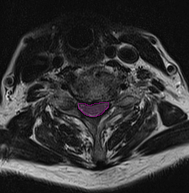

Στένωση αυχενικού σπονδυλικού σωλήνα με πίεση και παραμόρφωση του νωτιαίου μυελού. |